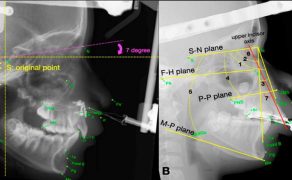

Streszczenie: Agenezja bocznych siekaczy szczęki jest najczęściej występującą anomalią rozwojową zębów. Postępowanie w przypadku braku siekacza bocznego polega na zamknięciu luki z wykorzystaniem kła jako namiastki siekacza albo na ortodontycznym utworzeniu przestrzeni dla uzupełnienia protetycznego. Uważa się, że – ponieważ luka występuje w obszarze estetycznym – odpowiednie podejście do potrzeb pacjenta wymaga starannej diagnostyki i planu leczenia. Taki problem jest dużym wyzwaniem dla ortodontów, protetyków i stomatologów ogólnych. Niniejsze doniesienie kazuistyczne opisuje postępowanie ortodontyczne u 22-letniej dorosłej pacjentki z brakiem górnego lewego bocznego siekacza i widoczną luką w odcinku przednim łuku zębowego, u której dokonano zamknięcia luki za pomocą lateralizacji kła i ukształtowano go w taki sposób, by stanowił namiastkę siekacza. Jednak w celu osiągnięcia optymalnej estetyki i poprawy zgryzu kluczowe są pewne modyfikacje w mechanice leczenia. Zamknięcie luki z wykorzystaniem lateralizacji kła wydaje się mniej inwazyjne, leczenie można zakończyć w stosunkowo krótkim czasie, a kolejny czynnik przemawiający na korzyść tej opcji to adaptacja przemieszczonego zęba do zmian, jakie z biegiem lat zachodzą w obrębie twarzy, bez konieczności uzupełnień protetycznych.

Łączne leczenie ortodontyczne i chirurgiczne ciężkiej wady zgryzu klasy III ze zgryzem krzyżowym przednim i tylnym

W niniejszej pracy kazuistycznej przedstawiono przypadek dorosłego pacjenta z ciężką szkieletową wadą zgryzu klasy III, z ewidentnym niedorozwojem szczęki i nadmiernie rozwiniętą żuchwą, co powodowało zgryz krzyżowy przedni i tylny, a także przesu...

60 lat innowacji w biomechanicznej chirurgii ortognatycznej: stan wiedzy i kierunki na przyszłość